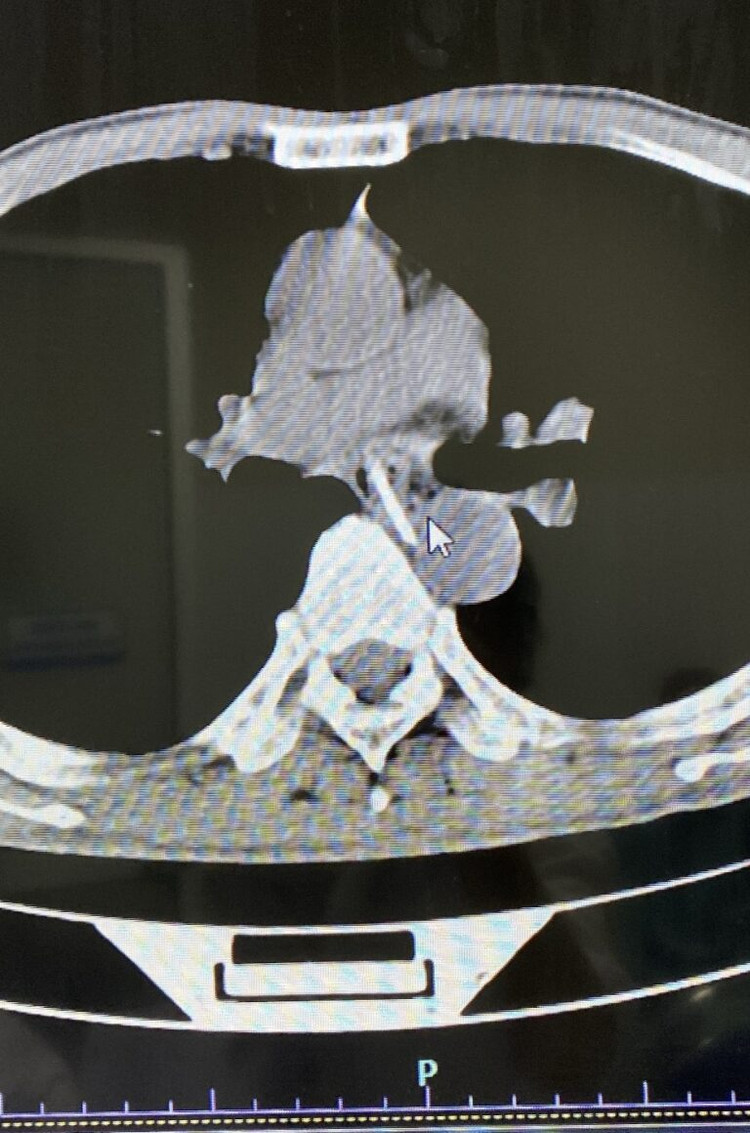

Tại đây, người bệnh được chụp cắt lớp vi tính và nội soi thực quản dạ dày phát hiện trong đoạn thực quản ngực có dị vật là xương gà lẫn thịt có kích thước khoảng 3cm. Xương có đầu sắc nhọn đâm vào thành thực quản.

| Hình ảnh chụp cắt lớp vi tính dị vật trong thực quản của người bệnh T. |